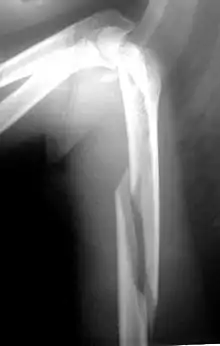

Рентгенограмма при переломе хирургической шейки плеча. Возможен перелом головки, отрыв малого или большого бугра, перелом анатомической и хирургической шейки плеча. Наиболее распространены переломы хирургической шейки, причём подавляющую часть пострадавших составляют люди пожилого возраста. Причиной перелома обычно становится падение на локоть, плечо или отведённую руку.

Пациент предъявляет жалобы на боли в области плечевого сустава. Вколоченные переломы сопровождаются нерезким отёком, болезненностью при попытке активных движений. Пассивные движения ограничены незначительно. При переломе со смещением клиническая картина более яркая. Пострадавшего беспокоят выраженные боли. Выявляется умеренный отёк, деформация области сустава и укорочение конечности. Определяется крепитация (хруст костных фрагментов). Диагноз уточняют по результатам рентгенографии.

При вколоченных переломах руку фиксируют специальной повязкой. При переломах хирургической шейки со смещением выполняют репозицию под местной анестезией. В последующем возможна фиксация повязкой по Турнеру или на отводящей шине, лейкопластырное или скелетное вытяжение. ЛФК назначают, начиная с 7-10 недели лечения. Срок иммобилизации составляет 6 недель.

Операция показана при нестабильных и оскольчатых переломах. Противопоказанием к операции является старческий возраст и тяжёлые хронические болезни.